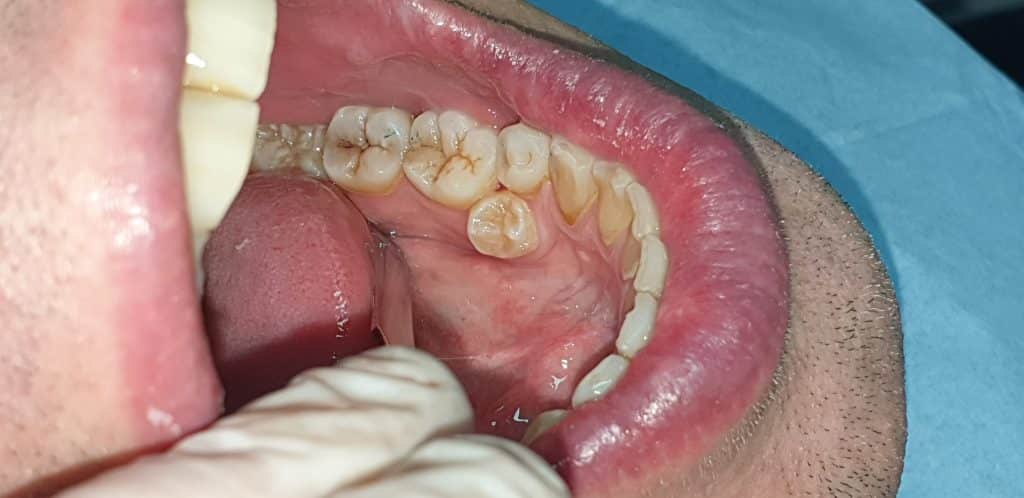

All’esame clinico si evince la posizione anomala del 3.5 e dopo aver effettuato OPT, si opta per l’avulsione dell’elemento dentario interessato.

L’avulsione ha presentato un discreto livello di difficoltà vista la posizione e lo stretto rapporto col 3.4, tanto da ipotizzare l’avulsione anche del 3.4.